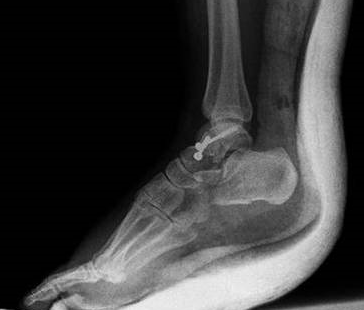

TALUS KIRIKLARI

Doktor Mehmet Subaşı

Talus ayak bileği eklemini oluşturan ayak kemiklerinden birisidir. Motor...

KALKANEUS KIRIKLARI

Kalkaneus, a...

PİLON KIRIKLARI

Ayak bileği, baldırın ana kemiği tibianın alt ucu, baldırın ince kemiği ...